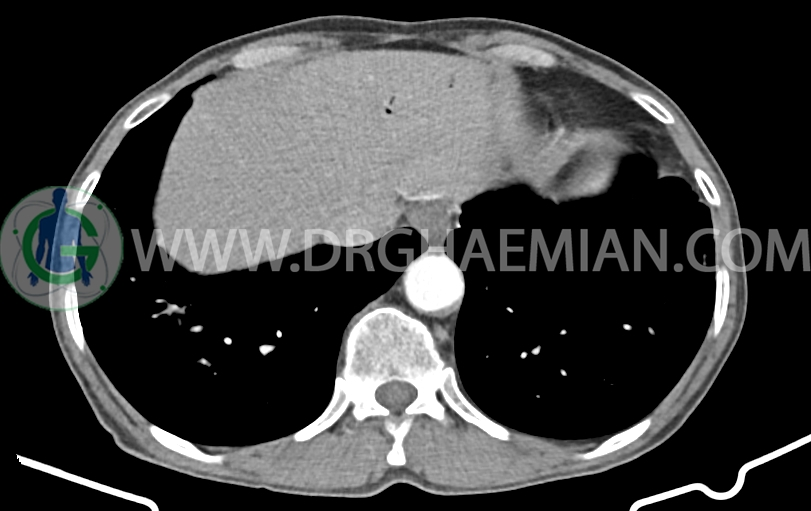

در سی تی اسکن اسپیرال ریه، مدیاستن و شکم و لگن با کنتراست خوراکی و وریدی (مولتی دیدکتور 16 با مقاطع ظریف و بازسازی های ساژیتال و کرونال) و مقایسه با سی تی اسکن 1401/06/06:

ندول های ground glass سنتری لوبولار پراکنده در دو طرفه همراه با تغیرات برونشکتازی سیستیک در LLL

باند فیبروتیک در لتروبازال LLL

مشهود است.